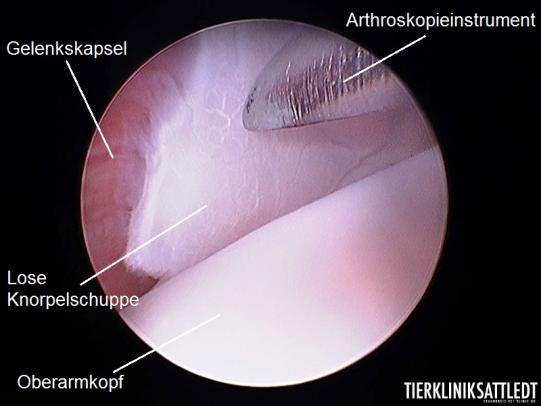

Bei diesem wachsenden Sporthund ist es wichtig, dass das Problem baldestmöglich aggressiv angegangen wird. Inox wird an die Orthopädieabteilung des Tierspitals Bern überwiesen, wo mittels Gelenksspiegelung die Diagnose bestätigt und das Problem operativ angegangen wird: Mit den ins Gelenk vorgeführten Instrumenten werden die losen Knorpelteile entfernt und der unterliegende, freiliegende Knochen debridiert (d.h. von losem Gewebe befreit). In der Folge wird der Knorpeldefekt im Zuge der Heilung durch Faserknorpel ersetzt.

Arthroskopische Aufnahme mit freundlicher Genehmigung der Tierklinik Sattledt/Österreich. Die Aufnahme stammt nicht von der Untersuchung bei "Inox".

OCD steht für Osteochondrosis Dissecans - eine Entwicklungsstörung des Knochen-Knorpelverbundes, bei welchem sich die schützende Knorpelschicht vom unterliegenden Knorpel löst, was starke Schmerzen bewirkt. Wird der abgelöste Knorpel chirurgisch entfernt, kann sich auf dem Defekt ein Ersatz- (oder Faser-)knorpel bilden. Das Gelenk wird auf Dauer trotzdem eine gewisse Arthrose (Abnützungserscheinung) entwickeln, gerade bei der Schulter-OCD ist die Schmerzlinderung durch den Eingriff aber häufig frappant.

Ein Video einer Schultergelenks-Arthroskopie bei OCD mit Entfernung des Knorpelfragmentes finden Sie hier .